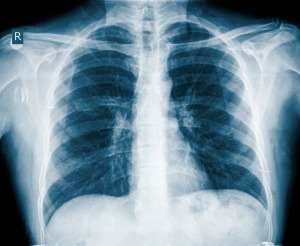

pneumonia

Selon une étude publiée récemment dans le Journal of the American Medical Association , l’hospitalisation en raison d’une pneumonie est un important facteur de risque de la maladie cardiovasculaire (MCV) chez les personnes d’âge moyen et âgées qui n’ont pas d’antécédent de maladie du cœur.